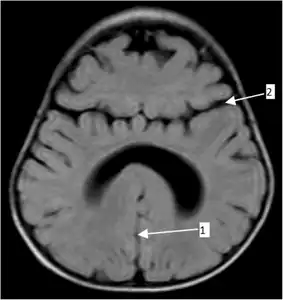

• Alobar holoprosencephaly, the most serious form, in which the brain fails to separate, is usually associated with severe facial anomalies, including lack of a nose and the eyes merged to a single median structure (see cyclopia).

• Semilobar holoprosencephaly, in which the brain's hemispheres have somewhat divided, is an intermediate form of the disease.

• Lobar holoprosencephaly, in which there is considerable evidence of separate brain hemispheres, is the least severe form. In some cases of lobar holoprosencephaly, the patient's brain may be nearly normal.

• Syntelencephaly, or middle interhemispheric variant of holoprosencephaly (MIHV), in which the posterior frontal lobe and the parietal lobe are not properly separated, but the rostro basal forebrain properly separates; it is possible that this is not a variant of HPE at all, but it is currently classified as such.[2]

• Agenesis of the corpus callosum, in which there is a complete or partial absence of the corpus callosum. It occurs when the corpus callosum, the band of white matter connecting the two hemispheres in the brain, fails to develop normally, typically during pregnancy. The fibers that would otherwise form the corpus callosum become longitudinally oriented within each hemisphere and form structures called Probst bundles.